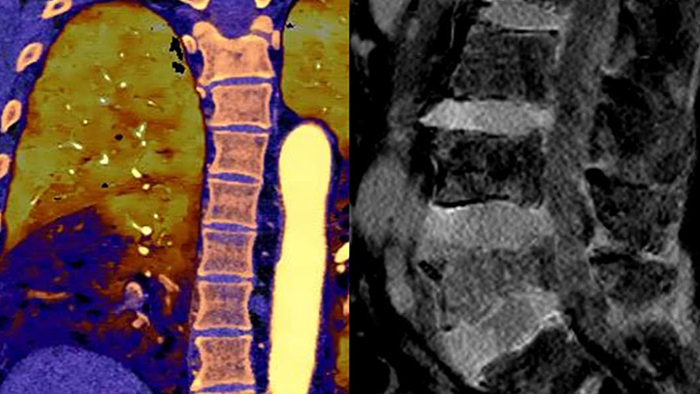

With detector-based spectral, you acquire multiple layers of data—conventional and spectral—within a single exposure and without special scan modes for improved tissue characterization and visualization.

Scan as usual A single scan for fast, low-dose conventional and spectral data for every patient, every time.

Always available 100% spectral, 100% of the time for results that are always available on-demand, even retrospectively.